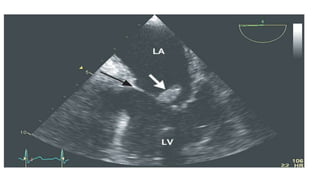

Large vegetation overthe tricuspid leaflet